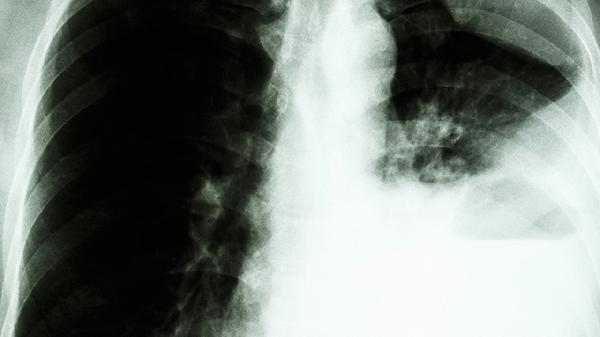

清肺排毒汤可能出现副作用,但整体概率较低。该方剂由中药复方组成,部分人群可能发生胃肠不适、过敏反应等,遵医嘱使用可降低风险。

清肺排毒汤作为新冠肺炎治疗推荐方剂,其副作用多与个体差异相关。常见表现包括轻度恶心、腹胀、食欲下降等消化道症状,多因方中麻黄、石膏等成分刺激胃肠黏膜所致,减少单次服用量或饭后温服可缓解。少数过敏体质者可能出现皮肤瘙痒、红疹等反应,与细辛、枳实等药材的挥发性成分有关,需立即停用并抗过敏处理。高血压患者需警惕方中麻黄碱可能导致的血压波动,服药期间应加强监测。另需注意,部分苦寒药材长期使用可能引发腹泻,疗程不宜超过14天。

罕见情况下,过量服用可能导致心悸、头晕等神经系统症状,或与方中药物相互作用加重肝肾负担。肝功能异常者需慎用柴胡,肾功能不全者应调整甘草剂量。孕妇及哺乳期女性因缺乏安全性数据,不推荐自行使用。儿童用药需严格按体重调整剂量,避免影响发育。

使用清肺排毒汤前应经中医师辨证,避免与阿司匹林、华法林等西药同服。服药期间宜清淡饮食,禁食生冷油腻,每日饮水量保持在1500毫升以上以促进代谢。若出现持续呕吐、呼吸困难等严重反应,需立即就医。药材质量与煎煮方法也直接影响安全性,建议选择正规医疗机构配药。